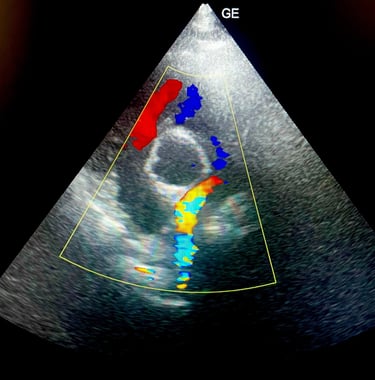

BADANIE ECHOKARDIOGRAFICZNE: badanie serca przy użyciu wysokiej klasy sprzętu ultrasonograficznego, który umożliwia wykrycie wad wrodzonych, chorób zwyrodnieniowych zastawek, powiększenia serca.